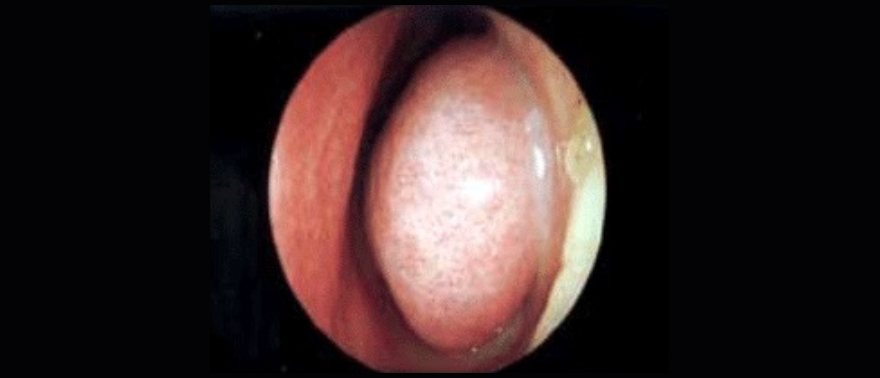

커져 있는 좌측 하비갑개 내시경 소견